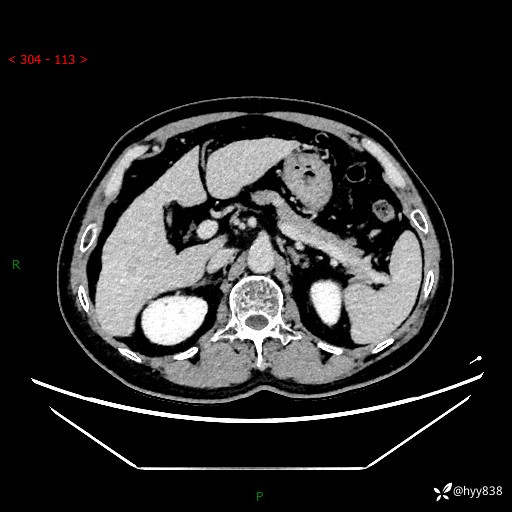

静脉期